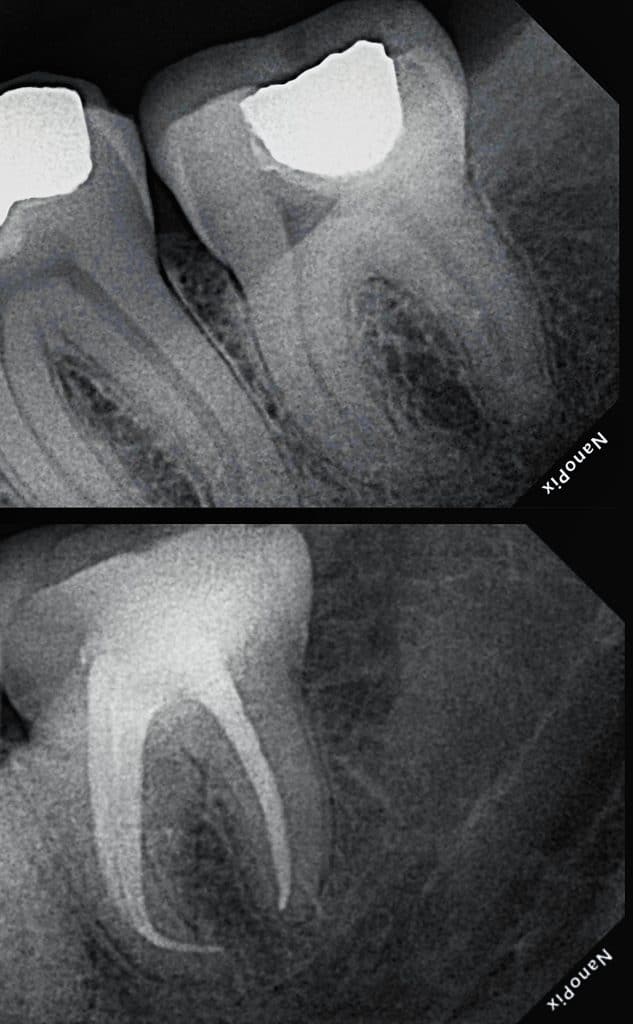

Ttt plan:

Endo ttt of lower 8 followed by compsite

And direct compsite to lower 7

After remove all amalgam

Endo ttt of lower 8

Cold hydraulic obturation with Bio ceramic sealer